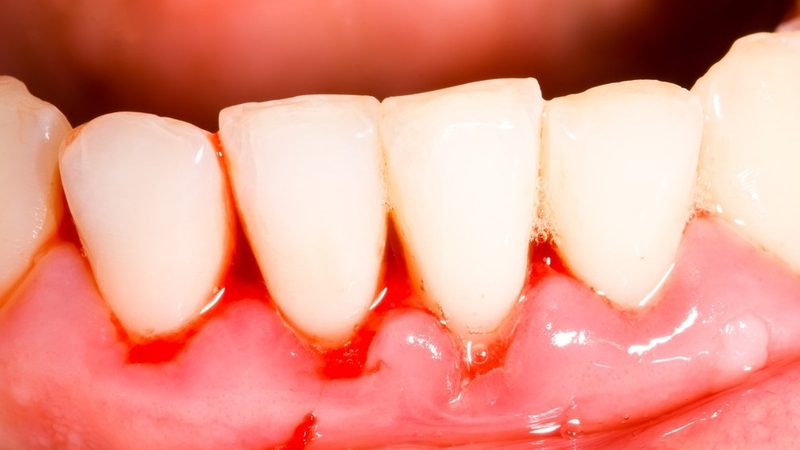

Người bị tụt lợi răng lung lay thường xuyên chảy máu chân răng, lợi sưng đỏ, răng nhạy cảm, ê buốt và khó chịu khi ăn uống. Điều này không chỉ ảnh hưởng nghiêm trọng đến sức khỏe răng miệng mà còn tác động tiêu cực đến sức khỏe toàn thân. Ăn uống trở nên không ngon miệng, gây chán ăn, cơ thể mệt mỏi, uể oải và có nguy cơ thiếu dinh dưỡng, thiếu máu cao.

Ngoài ra, nếu tụt lợi răng lung lay do lợi bị nhiễm trùng, ổ viêm nhiễm có thể lan sang các khu vực lân cận, gây nhiễm trùng máu và ảnh hưởng đến chức năng của các cơ quan khác.